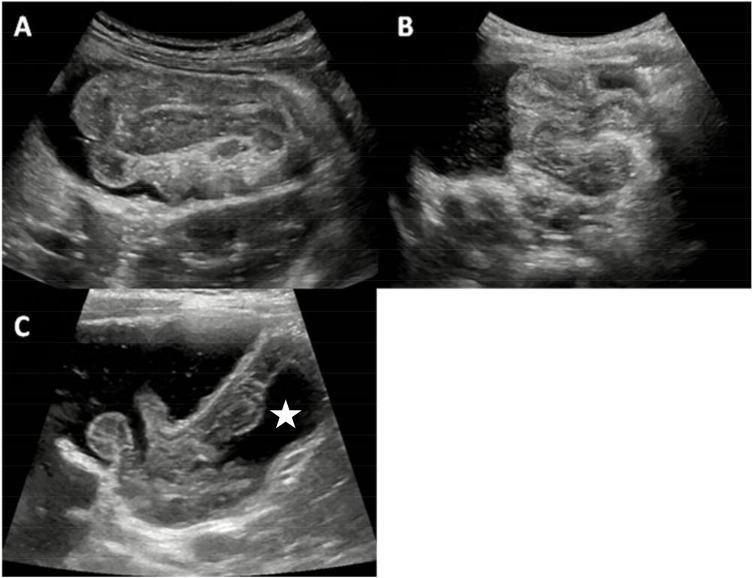

Intussusception is the most frequent pediatric abdominal emergency. Intestinal spasm, ischemia, necrosis and even death may occur without prompt diagnosis and treatment. The ultrasound-guided reduction by saline enema is a preferred non-surgical procedure for intussusception. Muscular relaxants can relieve the intestinal spasm and edema by relaxing the intestinal smooth muscle, which may facilitate the treatment of intussusception. However, controversy persists on whether muscular relaxants are effective in the procedure. Therefore, the purpose of our study was to assess the efficacy of atropine known as a muscular relaxant in ultrasound-guided reduction by saline enema in children with intussusception. All patients with intussusception diagnosed and treated in our department from July 2016 to February 2018 were included. Four hundred and thirty-seven children were enrolled and randomly divided into two groups: an atropine group and a control group. Intramuscular atropine at a dose of 0.02 mg per kilogram of body weight was administrated 15 min before ultrasound-guided reduction by saline enema in the atropine group. In the control group, the ultrasound-guided reduction was performed without using any muscular relaxants. The success rate, duration of the reduction, volume of saline, maximum intra-rectal pressure and complications were recorded and compared between the two groups. The success rate was 95.9% (212 out of 221) and 94.9% (205 out of 216) in the atropine group and the control group, respectively. No significant difference was observed in the success rate between the two groups ( > 0.05). The duration of reduction was significantly lower in the atropine group than in the control group ( < 0.01). The volume of saline was also significantly lower in the atropine group than in the control group ( < 0.05). The maximum intra-rectal pressure showed no difference between the two groups ( > 0.05). Atropine premedication can facilitate ultrasound-guided reduction by saline enema in children with intussusception, by reducing the duration of reduction and the volume of saline in the procedure.

肠套叠是最常见的儿科腹部急症。若不及时诊断和治疗,可能会发生肠道痉挛、缺血、坏死甚至死亡。超声引导下盐水灌肠复位是治疗肠套叠首选的非手术方法。肌肉松弛剂可通过松弛肠道平滑肌来缓解肠道痉挛和水肿,这可能有助于肠套叠的治疗。然而,对于肌肉松弛剂在该治疗过程中是否有效仍存在争议。因此,我们研究的目的是评估作为肌肉松弛剂的阿托品在超声引导下盐水灌肠复位治疗儿童肠套叠中的疗效。纳入2016年7月至2018年2月在我科诊断并治疗的所有肠套叠患儿。共纳入437例儿童,随机分为两组:阿托品组和对照组。阿托品组在超声引导下盐水灌肠复位前15分钟,按每公斤体重0.02mg的剂量肌肉注射阿托品。对照组在不使用任何肌肉松弛剂的情况下进行超声引导下复位。记录并比较两组的成功率、复位持续时间、盐水量、直肠内最大压力及并发症。阿托品组和对照组的成功率分别为95.9%(221例中的212例)和94.9%(216例中的205例)。两组成功率差异无统计学意义(>0.05)。阿托品组的复位持续时间显著低于对照组(<0.01)。阿托品组的盐水量也显著低于对照组(<0.05)。两组直肠内最大压力差异无统计学意义(>0.05)。阿托品预处理可通过缩短复位持续时间和减少术中盐水量,促进超声引导下盐水灌肠复位治疗儿童肠套叠。